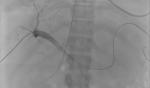

Under ultrasound guidance, transjugular access as well as percutaneous transhepatic access was obtained. An 8 F sheath was inserted into the right internal jugular vein. A 20-gauge Chiba needle was percutaneously inserted into the right portal vein via a right anterolateral intercostal approach (Figure 1). Injected contrast confirmed positioning before advancing a 6 F sheath into the right portal vein (Figure 2). Venography confirmed a massive spontaneous left-sided splenorenal shunt (Figure 3).

Figure 1: portal venography following needle introduction into the portal vein during DIPS creation